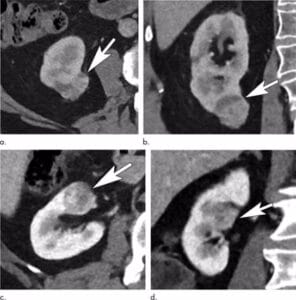

Para lograr un diagnóstico del cáncer de riñón, lógicamente, en una primera instancia, se debe realizar una historia clínica detallada con una exploración física completa. Habitualmente ya se dispone de una prueba de imagen. Pero es necesario un TAC abdominal y torácico, así como unos análisis de sangre.

Con estos datos es frecuente que se pueda ofrecer un tratamiento para el tumor y no sea necesario más pruebas analíticas. Ocasionalmente, para poder planificar un tratamiento óptimo, sería necesario la realización de una Resonancia Magnética, un angioTAC o incluso un PET.